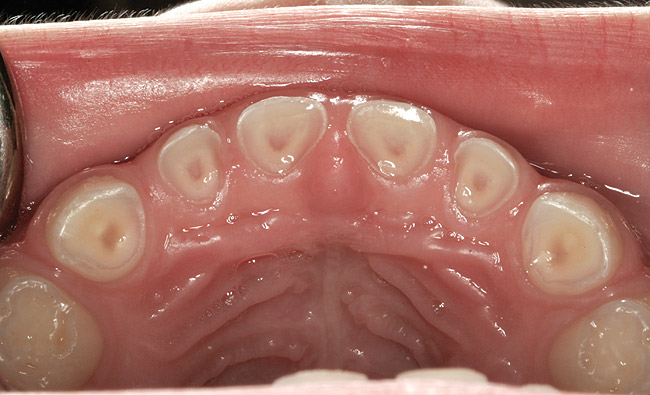

The pattern for bone growth resides not in the bone itself but rather in the soft tissue and muscle that encase the bone.42 Oral-facial muscle tone and tongue tonicity create a framework for normal development of the nasomaxillary complex and mandible.43 SDB is noted in children with pathologic hypotonia of facial and tongue muscles. Children born with a normal palate and oral-facial hypotonia will develop a high, narrow palate over the first year of life (Figure 3 and Figure 4). Children born with a high, narrow palate have hypotonia at birth. These myofunctional changes may be detected in utero.43

(21.) Six-year-old male presents nocturnal bruxism, habitual snoring, and behavioral issues. PSG reports an AHI of 9.6/hr and respiratory effort–related arousal (RERA) of 14.2/hr (Case provided by Kathy French, DDS).

Figure 21

Without esophageal pressure monitoring to demonstrate the increase respiratory effort, bruxism activity may not be recognized as being associated with a respiratory event.71,72 This RERA-related phenomenon was verified in a study of 50 pediatric subjects with an inclusion criteria of sleep-related tooth wear.73 No significant statistical association was found between AHI and the severity of bruxism. However, when respiratory effort–related arousals were added to the AHI, a statistically significant association was found. The bruxing events acted to protect the airway rather than to resolve an obstruction. Bruxism should rise with UARS, habitual snoring, and occasional snoring, because negative pressure and respiratory effort drives the action. The researchers concluded that pediatric sleep-related tooth wear could be used as a marker for SDB. Currently, no other healthcare provider is more equipped to evaluate and monitor pediatric nocturnal tooth wear than the dental practitioner (Figure 21 and 22).